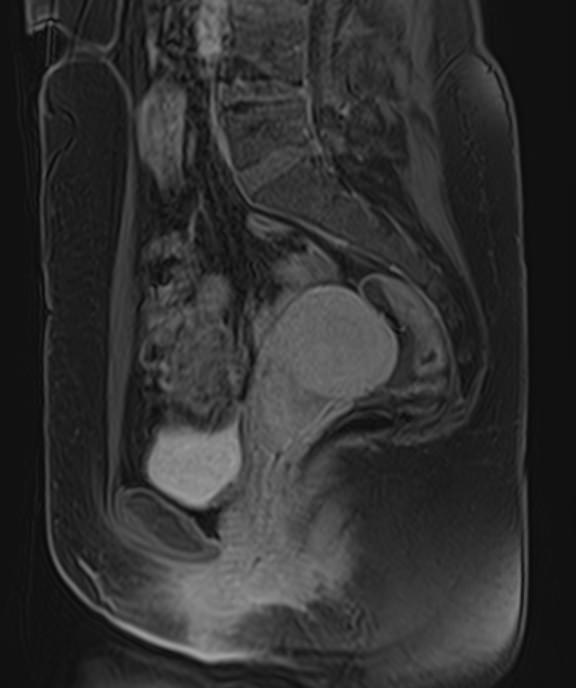

Стандартный протокол сканирования не предусматривает использование контраста. Однако при необходимости уточнения патологических изменений в органе, в случае дифференциальной диагностики, особенно при подозрении на опухоль, обязательным является применение контрастного усиления.

Для этого в вену вводится контрастное вещество на основе металла гадолиния. Контраст «высвечивает» очаги поражения размерами от 1 мм, что позволяет диагностировать патологический очаг в самом начале развития. Ранняя диагностика онкозаболеваний имеет важнейшее значение для жизни и здоровья пациента.

Наиболее часто томографию матки применяют в комплексной диагностике и лечении новообразований. Процедура позволяет с высокой точностью определить локализацию, размеры и влияние опухоли на окружающие ткани, а также провести первичную дифференциацию добро- и злокачественных структур (по форме, строению, особенностям накопления контраста и пр.). Динамический контроль методом МРТ позволяет объективно оценить эффективность терапевтической тактики.